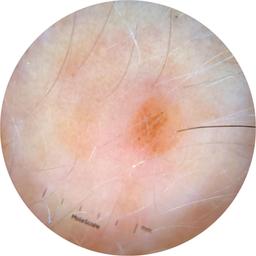

ISIC_6769723

Information

2013 x 2013

Clinical

Field Value

acquisition_day 298

age_approx 45

anatom_site_1 Lower extremity

anatom_site_general lower extremity

concomitant_biopsy False

diagnosis_1 Benign

diagnosis_confirm_type single image expert consensus

family_hx_mm True

fitzpatrick_skin_type I

image_manipulation instrument only

image_type dermoscopic

lesion_id IL_0892257

patient_id IP_5324562

personal_hx_mm True

sex female